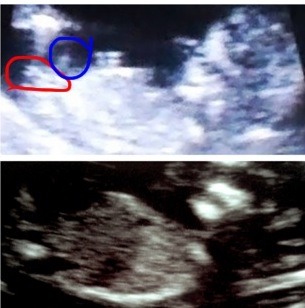

Ok -so I can't stop staring at my 12 wk, 5 day scan. I have asked ynwa if I can use one of her pics to compare to mine (hers is confirmed girl). Ynwa's little one is on top and mine is on the bottom. I'm posting them regular and then also posting one where the nubs are circled. Please help my craziness LOL! My gender scan is on Dec 1st!!!!

Attachment 6386